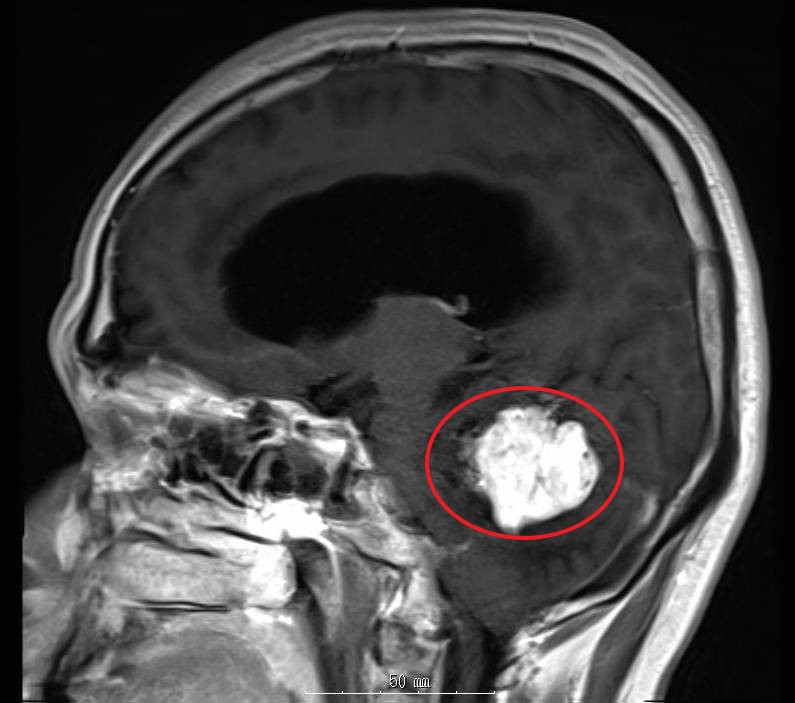

松果体近傍部腫瘍

松果体近傍部腫瘍は小脳テントを経て病変部にアプローチするのが主流です。この症例も同アプローチにて摘出しました。

術前MRI画像